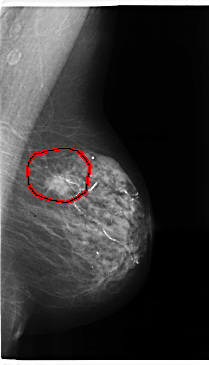

ics_version 1.0 filename C-0196-1 DATE_OF_STUDY 16 9 1996 PATIENT_AGE 83 FILM FILM_TYPE REGULAR DENSITY 2 DATE_DIGITIZED 26 3 1998 DIGITIZER LUMISYS LASER SEQUENCE LEFT_CC LINES 4728 PIXELS_PER_LINE 2536 BITS_PER_PIXEL 12 RESOLUTION 50 OVERLAY LEFT_MLO LINES 4736 PIXELS_PER_LINE 2712 BITS_PER_PIXEL 12 RESOLUTION 50 OVERLAY RIGHT_CC LINES 4616 PIXELS_PER_LINE 2824 BITS_PER_PIXEL 12 RESOLUTION 50 NON_OVERLAY RIGHT_MLO LINES 4672 PIXELS_PER_LINE 2712 BITS_PER_PIXEL 12 RESOLUTION 50 NON_OVERLAY |

FILE: C_0196_1.LEFT_CC.OVERLAY TOTAL_ABNORMALITIES 1 ABNORMALITY 1 LESION_TYPE MASS SHAPE OVAL MARGINS SPICULATED ASSESSMENT 5 SUBTLETY 5 PATHOLOGY MALIGNANT TOTAL_OUTLINES 1 BOUNDARY |